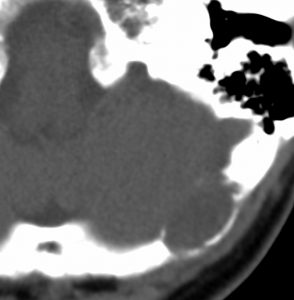

静脈洞交会 confluence に浸潤しているものです。直静脈洞は閉塞しています。右のMRIでは,ガドリニウム増強像が強弱まばらになっています。髄膜腫と診断したいのですが,ちょっと何かが違うというのがSFTです。硬膜や骨や脳に浸潤性格を有します。亜全摘出して術後に54グレイの放射線治療をしました。

5年後に小脳内に再発しました。全摘出したのですが,その後もあちこちに再発を繰り返しています。最初はグレード2でしたが,再発を繰り返すと増大速度が速くなり,再発までの期間が短くなり,多発性再発となってきます。